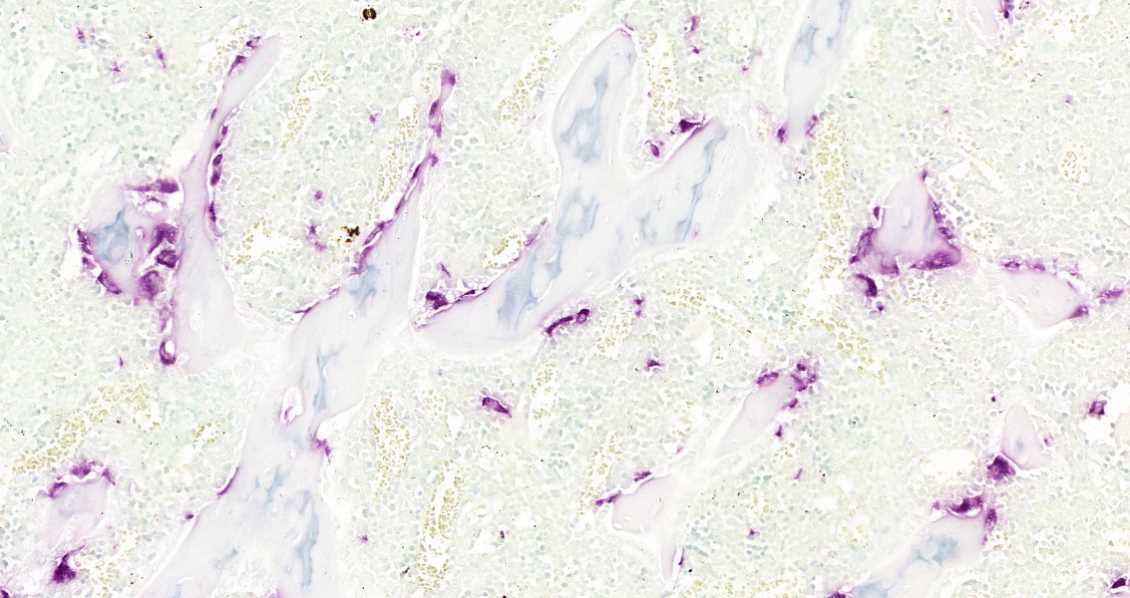

三、染色结果判读:阳性颗粒呈紫红色,细胞核呈蓝色或绿色。

实验结果展示